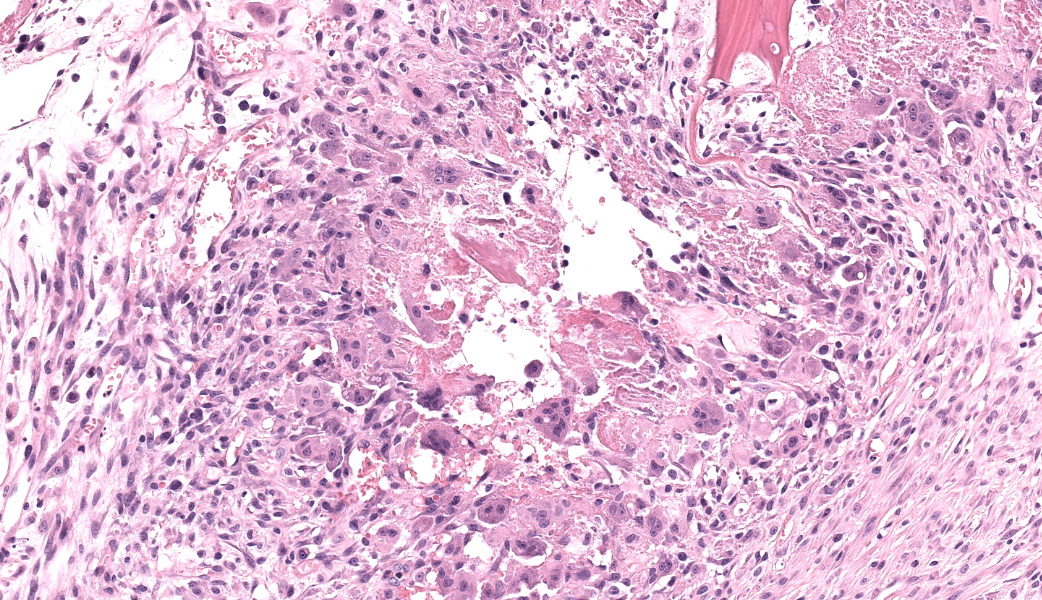

Femoral head: Affecting approximately 30-50% of the epiphysis from the subchondral aspect of the articular cartilage to the physis, there is a focally extensive area of osteonecrosis characterized by bony trabeculae which are irregular and brightly eosinophilic with loss of differential staining. There is loss of both osteocytes within lacunae and osteoblasts lining trabeculae in this region. Along the margins of the necrotic area, multiple bone trabeculae are fragmented and/or have scalloped margins with osteoclasts in Howship’s lacunae (osteolysis). The intertrabecular spaces within and at the periphery of the necrotic area contain variably amounts of amorphous eosinophilic matrix (fibrin), occasional neutrophils and macrophages and/or loosely arranged myxomatous to collagenous matrix with variable numbers of plump spindle cells and capillaries (fibroplasia). Occasionally, there are also finer, irregular trabeculae of paler staining or partially mineralized bone (woven bone). Adjacent viable trabeculae are lined by numerous active osteoblasts (remodeling) and are sometimes laced with wavy basophilic lines (resting / resorption lines). The articular cartilage is fragmented (likely artefact).Contributor's Morphologic Diagnoses:

Differentiating necrotic bone from normal bone can be challenging, but one of the key features to look for is the loss of osteocytes from lacunae.5 Osteocytes either become pyknotic and hypereosinophilic or disappear entirely, and you can best convince yourself this is a real change (and not just a staining artifact) by comparing an area of suspected necrosis to an area of less affected or normal bone where the osteocytes will still be in their lacunae and have a nice, basophilic nucleus. Another useful way to determine osteonecrosis is to assess the bone marrow. In necrotic bone, there is usually histologic loss of marrow elements secondary to ischemia, which will manifest as a loss of differential staining with retention of architecture within the marrow.